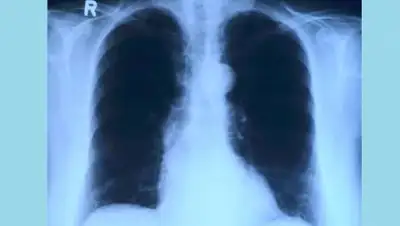

Если у пациента кашель более 2-х недель, резкое похудание, потливость, боли в грудной области, кровохарканье (не во всех случаях), слабость, быстрая утомляемость, повышение температуры тела. то это вероятные симптомы туберкулеза. Это инфекционное заболевание, вызываемое микобактериями туберкулеза, больше известными как бациллы или палочки Коха. Поражаются преимущественно легкие(80%) реже другие органы (20%). Ранняя диагностика и своевременное лечение - ключевой момент в борьбе с туберкулезом. - сказала врач-фтизиатр поликлиники ГКБ №7 Алматы Каракоз Утемуратова.

Туберкулез остается одной из самых смертоносных инфекций и одной из ведущих причин смертности населения в мире. Согласно информации ВОЗ от туберкулеза ежедневно погибает в мире около 4000 человек. В Казахстане с каждым годом регистрируется все меньше случаев заболевания туберкулезом, и уровень смертности среди больных продолжает падать. Но туберкулез не исчез. Общее число пациентов, страдающих от туберкулеза, все еще высоко.